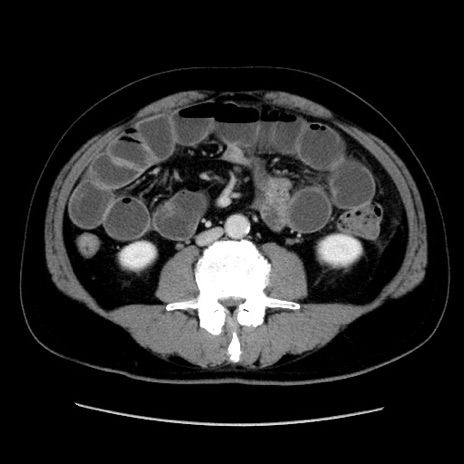

症例16(横断像)

【症例】 70歳代男性

【主訴】 腹痛、嘔吐

【現病歴】 約1ヶ月前より間欠的に腹痛と嘔吐あり、当院消化器内科を受診したところCTで多発する肝臓のLDAを指摘され、精査中であった。以降は消化器症状は安定していたが、2日前より嘔気と腹痛があり、同日より排便・排ガスが消失した。改善認めず、 本日、救急外来を受診した。

【身体所見】意識清明・会話良好、BT 36.3℃、BP 127/80mmHg、 P 80bpm、腹部:膨満あり、平坦・軟、上腹部正中および下腹部正中に圧痛あり、反跳痛なし、筋性防御なし。

【データ】WBC 7200、CRP 0.77